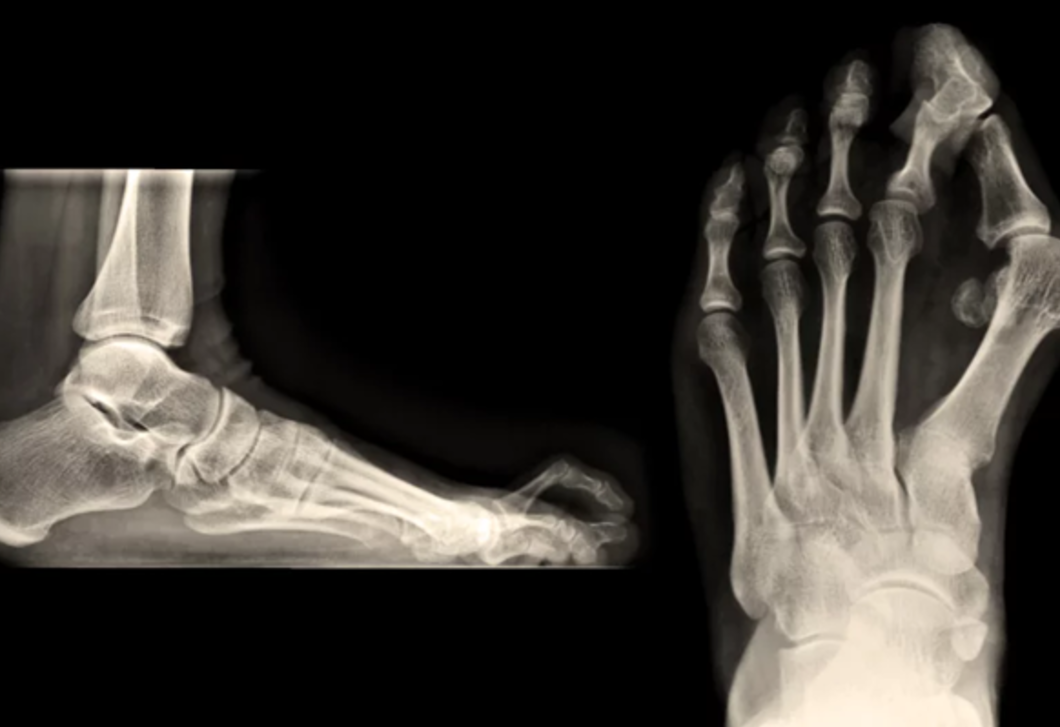

Mit tegyél a bütyök és kalapácsujj ellen?

© Dr. Rose Magánkórház

Dr. Kiss Dániel ortopéd-traumatológus, a  Dr. Rose Magánkórház szakorvosa szerint a bütyök és a kalapácsujj a leggyakoribb lábdeformitások közé tartoznak, mégis sokan csak akkor fordulnak orvoshoz, amikor a probléma már komoly fájdalmat okoz. A megelőzés, a korai felismerés és a szakszerű kezelés hosszú távon nemcsak a fájdalmat csökkenti, hanem a mozgásminőséget is jelentősen javítja.

A kalapácsujj legtöbbször a bütyökkel együtt jelenik meg, hiszen gyakran a deformált nagylábujj kényszeríti rossz pozícióba a szomszédos ujjakat. „A kalapácsujj valójában egy láncreakció eredménye, ahol a láb statikájának megborulása fokozatosan torzítja el a lábujjak helyzetét” – mondja Kiss doktor.